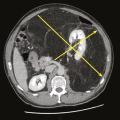

Traitements médicaux des sarcomes osseux, des sarcomes des tissus mous et des GIST

Les molécules utilisées dans le traitement médical des sarcomes diffèrent selon le type d’atteinte, la localisation et la phase concernée. La question des traitements d’entretien reste ouverte.